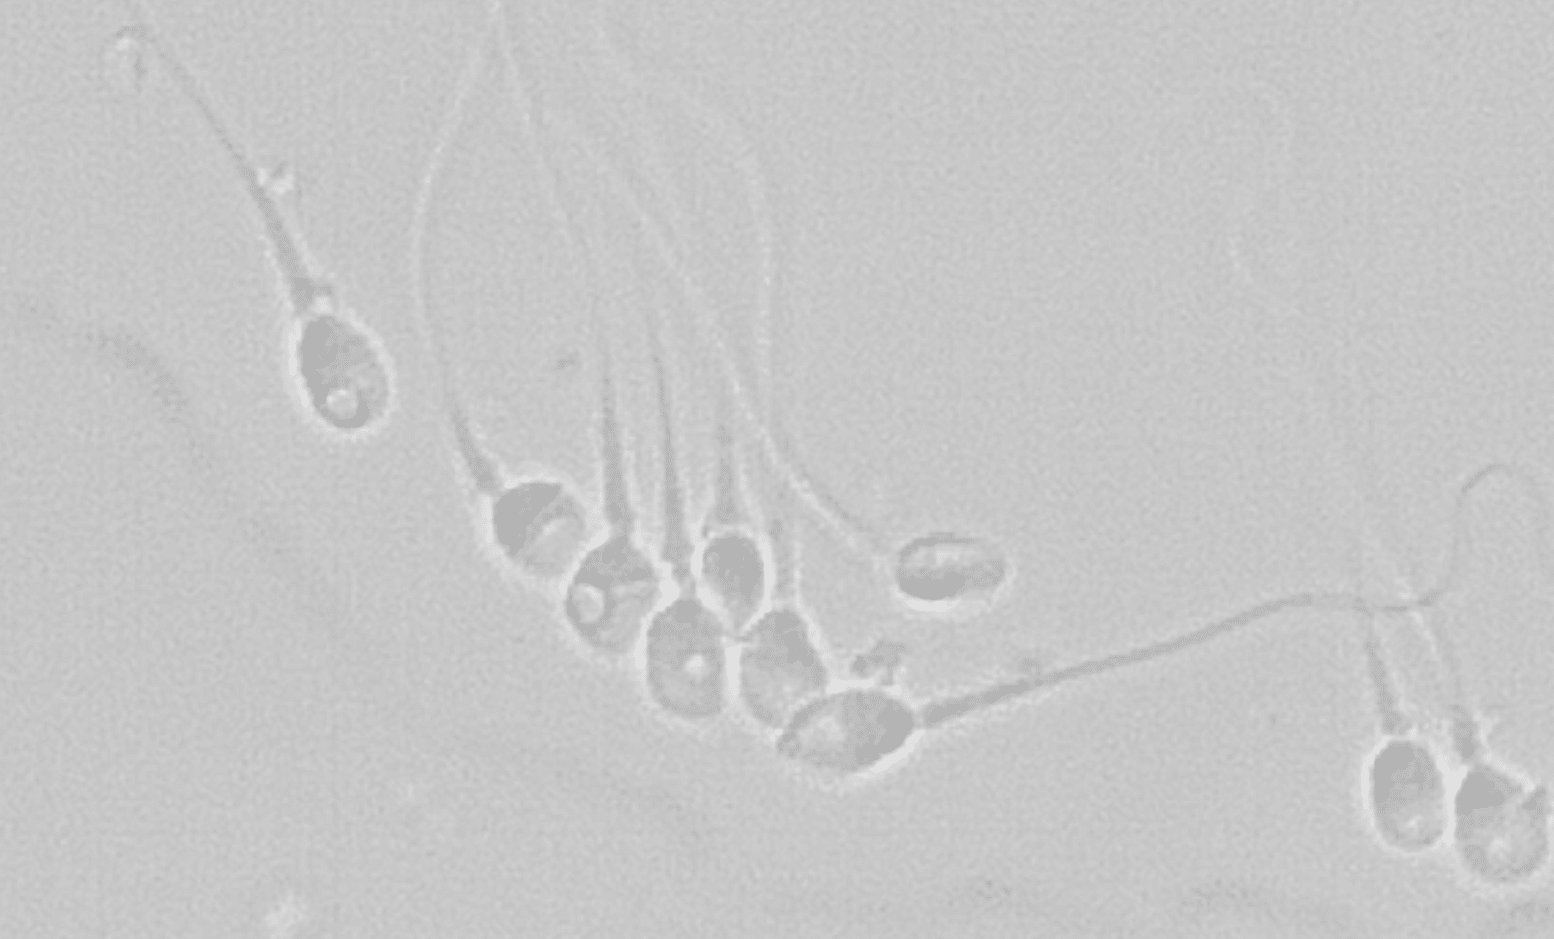

Bióloga - embrióloga

Responsable del Laboratorio de Reproducción Asistida Ginemed Huelva

Partes del óvulo: estructura y función